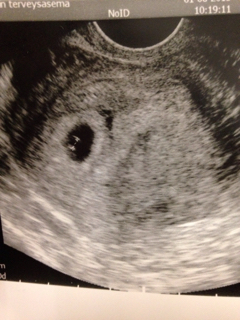

Mulla tehtiin lääkärineuvolassa ultra alakautta 1.6 kun ei ollu tietoa koska menkat ollu jne. Se lekuri sitten ilmoitti että oli n. rv 5-6 no olis suoraan sanonu että 5. Mutta kyllä mulla sielä näky pieni reikä, sikiöpussi.. Niin tässä on vielä kuva sieltä että eiköhän sullakin joku tommonen näy.. :) ..Neuvolaan soitettu ja varasi heti to ultran! Öö näkyykö rv4-5 mitään? Jännä toiminta tässä kaupungissa kun neuvolassa on ultra saatavilla aina